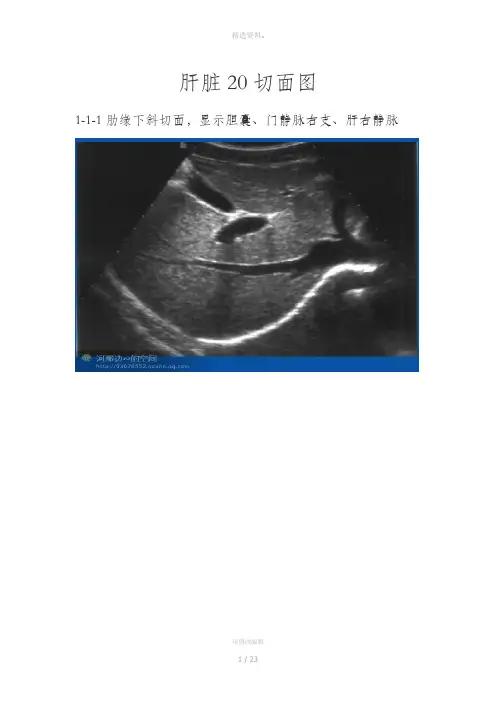

肝脏20切面图1-1-1肋缘下斜切面,显示胆囊、门静脉右支、肝右静脉11-I-2肋缘下斜切面,显示下腔静脉、肝左静脉、肝中静脉、肝右静脉21-1-3剑下肝左叶斜切面,显示肝圆韧带、腹主动脉、下腔静脉、门静脉31-1-4剑下肝左叶斜切面,显示肝左叶、肝尾状叶、静脉韧带、腹主动脉、下腔静脉41-1-5右第五肋间斜切面,显示门静脉、肝左静脉外下段、门静脉左支外上段、肝左静脉51-1-6右第六或第七肋间斜切面,显示右肝管、肝总管及胆总管、肝动脉、门静脉、下腔静脉6管、右肝管、下腔静脉、肝右静脉7左肝管、右肝管、下腔静脉、肝圆韧带81-1-9经下腔静脉肝左叶矢状切面,显示下腔静脉、门静脉矢状部、肝左静脉、左叶间静脉、肠系膜上静脉91-1-10经腹主动脉肝左叶矢状切面,显示腹主动脉、肝左静脉、门静脉、脾动脉、脾静脉、腹腔动脉101-1-11剑下肝左叶斜切面静脉左支矢状部、显示胆囊、肝圆韧带、门静脉左支横部、左外叶下段支、左外叶上段支、静脉韧带、下腔静脉111-1-12肝左叶矢状切面,显示下腔静脉、门静脉、肝左静脉、静脉韧带121-1-13肝右叶矢状切面,显示下腔静脉、肝中静脉、门静脉右支、右肾静脉、右肾动脉131-1-14肝右叶纵切面,显示与右肾的界面141-1-15肝右叶纵切面,显示隔顶部与胸腔15161-1-16肝左叶横切面,显示静脉韧带、腹主动脉、下腔静脉、尾状叶171-1-17肝左叶横切面,显示肝圆韧带181-1-18右肝横切面,显示门静脉左右支191-1-19肋缘下右肝横切面,显示右肝下缘201一1-20肝右叶横切面,显示隔顶部与胸腔2122。

肝脏20切面图1-1-1肋缘下斜切面,显示胆囊、门静脉右支、肝右静脉1-I-2肋缘下斜切面,显示下腔静脉、肝左静脉、肝中静脉、肝右静脉1-1-3剑下肝左叶斜切面,显示肝圆韧带、腹主动脉、下腔静脉、门静脉1-1-4剑下肝左叶斜切面,显示肝左叶、肝尾状叶、静脉韧带、腹主动脉、下腔静脉1-1-5右第五肋间斜切面,显示门静脉、肝左静脉外下段、门静脉左支外上段、肝左静脉1-1-6右第六或第七肋间斜切面,显示右肝管、肝总管及胆总管、肝动脉、门静脉、下腔静脉1-1-7经第一肝门右肋下斜切面,显示胆囊、门静脉、左肝管、右肝管、下腔静脉、肝右静脉1-1-8经第一肝门右肋下斜切面,显示腹主动脉、门静脉、左肝管、右肝管、下腔静脉、肝圆韧带1-1-9经下腔静脉肝左叶矢状切面,显示下腔静脉、门静脉矢状部、肝左静脉、左叶间静脉、肠系膜上静脉1-1-10经腹主动脉肝左叶矢状切面,显示腹主动脉、肝左静脉、门静脉、脾动脉、脾静脉、腹腔动脉1-1-11剑下肝左叶斜切面静脉左支矢状部、显示胆囊、肝圆韧带、门静脉左支横部、左外叶下段支、左外叶上段支、静脉韧带、下腔静脉1-1-12肝左叶矢状切面,显示下腔静脉、门静脉、肝左静脉、静脉韧带1-1-13肝右叶矢状切面,显示下腔静脉、肝中静脉、门静脉右支、右肾静脉、右肾动脉1-1-14肝右叶纵切面,显示与右肾的界面1-1-15肝右叶纵切面,显示隔顶部与胸腔1-1-16肝左叶横切面,显示静脉韧带、腹主动脉、下腔静脉、尾状叶1-1-17肝左叶横切面,显示肝圆韧带1-1-18右肝横切面,显示门静脉左右支1-1-19肋缘下右肝横切面,显示右肝下缘1一1-20肝右叶横切面,显示隔顶部与胸腔THANKS !!!致力为企业和个人提供合同协议,策划案计划书,学习课件等等打造全网一站式需求欢迎您的下载,资料仅供参考!。

肝脏20切面图

i-i-i肋缘下斜切面,显示胆囊、门静脉右支、肝右静脉